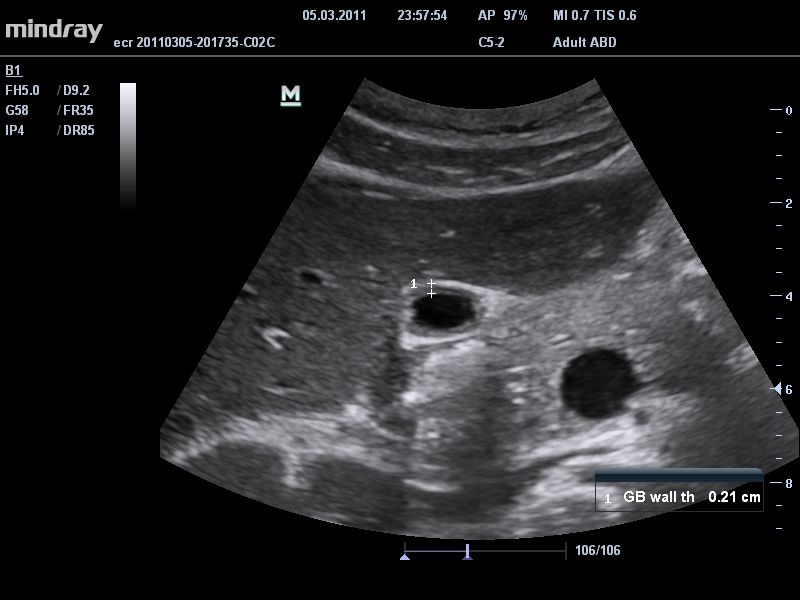

Ультразвуковая система Mindray DC-T6 – это инновационный аппарат для проведения высокого уровня диагностики с качественной визуализацией и широким спектром применения. Платформа рекомендована для использования в коммерчески многопрофильных медицинских учреждениях и государственных лечебных клиниках.

• THI со сдвигом фазы: увеличивает четкость визуализации желчного и мочевого пузыря и повышает отношение сигнал-шум.